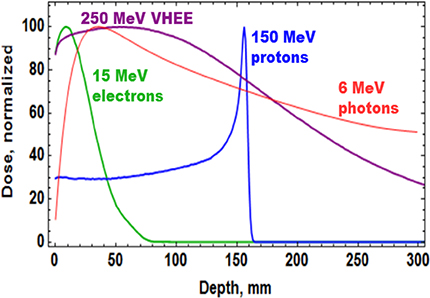

Low-energy electrons have historically been used to treat cancer for more than five decades, but mostly for the treatment of superficial tumours given their very limited penetration depth. However, this limitation can be overcome if the electron energy is increased between 50 and 200 MeV (i.e., very high-energy electrons, VHEE; figure 5.1). With the recent developments of high-gradient normal conducting (NC) radio frequency (RF) linac technology (figure 5.2) (CLIC Project n.d.) or even the novel acceleration techniques such as the laser-plasma accelerator (LPA) (figure 5.3), VHEE offer a very promising option for anticancer RT. Theoretically, VHEE beams offers several benefits. The ballistic and dosimetry properties of VHEE provide small-diameter beams that could be scanned and focused easily, enabling finer resolution for intensity-modulated treatments than is possible with photons beams. Electron accelerators are more compact and cheaper than proton therapy accelerators. Finally, VHEE beams can be operated at very high-dose rates and fast electromagnetic scanning providing uniform dose distribution throughout the target and allowing for unforeseen RT modalities in particular the FLASH-RT.

Figure 5.1. Dose profile for various particle beams in water (beam widths r = 0.5 cm).

Standard image High-resolution imageFLASH-RT is a paradigm-shifting method for delivering ultra-high doses within an extremely short irradiation time (tenths of a second). The technique has recently been shown to preserve normal tissue in various species and organs while still maintaining anti-tumour efficacy equivalent to conventional RT at the same dose level, in part due to decreased production of toxic reactive oxygen species. The 'FLASH effect' has been shown to take place with electron, photon, and more recently for proton beams. However, the potential advantage of using electron beams lies in the intrinsically higher dose that can potentially be reached compared to protons and photons, especially over large areas as would be needed for large tumours. Most of the preclinical data demonstrating the increased therapeutic index of FLASH has used a single fraction and hypo-fractionated regimen of RT and using 4–6 MeV electron beams, which do not allow treatments of deep-seated tumours and trigger large lateral penumbra (figure 5.4). This problem can be solved by increasing the electron energy to values higher than 50 MeV (VHEE), where the penetration depth is larger.